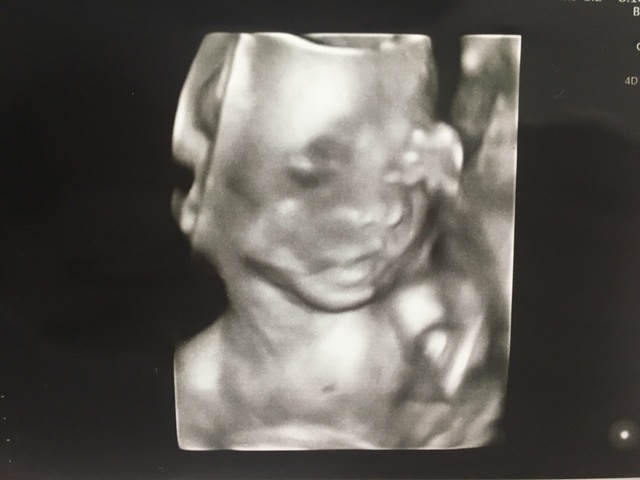

21週0日(21w0d・女の子)|晴香 さん(23歳)

エコー写真撮影時のエピソード:

エコーではいつも手で顔を隠していたので、なかなか顔を見ることができませんでした。この写真は、初めて子どもの顔がエコーに映った時のものです。

パパ似だなぁとか言いながら、夫婦で何度も見た写真です。この写真を見ると出産の不安は無くなり、会えるのがとても楽しみになりました。